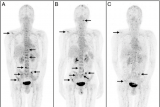

纽瑞特医疗完成68Ga-NRT6020注射液及177Lu-NRT6020注射液安全性和耐受性I期临床试验首例受试者入组

近日,由成都纽瑞特医疗科技股份有限公司(以下简称纽瑞特医疗)申办的一项评价68Ga-NRT6020注射液及177Lu-NRT6020注射液在FAP阳性晚期恶性实体瘤受试者中的安全性和耐受性的I期临床试验于复旦大学附属肿瘤医院(主要研究者:宋少莉教授、张剑教授)成功完成首例受试者给药,这标志着该项临床研究已从筹备阶段正式进入实质性实施阶段,也是68Ga-NRT6020注射液及177Lu-NRT6020注射液诊疗一体化开发过程中的一个重要里程碑。关于FAPFAP是具有细胞... 2025-12-05 核医学放射性药物核医药